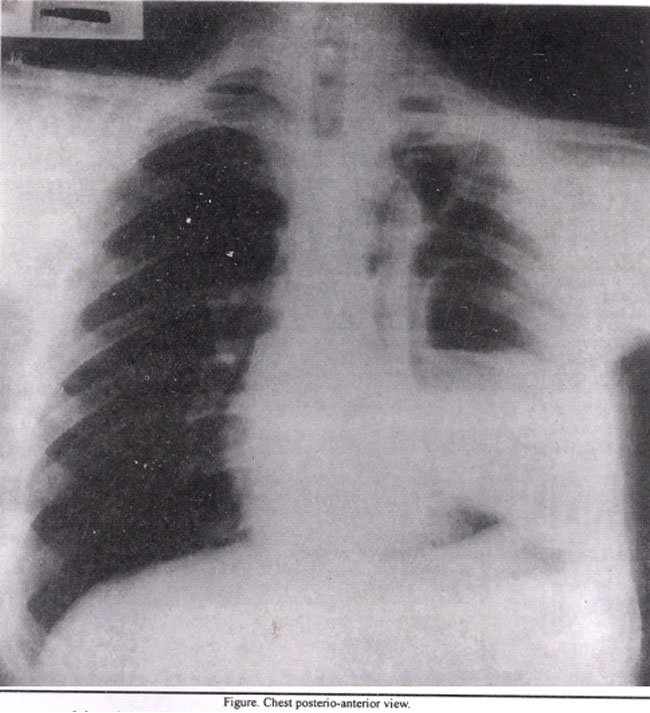

A 22 years old male presented with complaints of high grade fever for one month and breathlessness for one week. On examination his temperature was 102°F. He was tachypnic and there was reduced air entry in left hemithorax. Leukocyte count and E.S.R. were elevated. An Xray chest showed a 13.5x8.5cm oval shape cavity in left hemithorax with an air-fluid level (Figure).

On computed tomography the cavity had thick wall, the inner wall was irregular. Under ultrasound guidance, a chest tube was put in and thick pus was drained. Patient was given intravenous antibiotics followed by oral antibiotics. The chest tube was removed following complete drainage of abscess. Patient recovered completely.

Diagnosis: Pyogenic lung abscess.